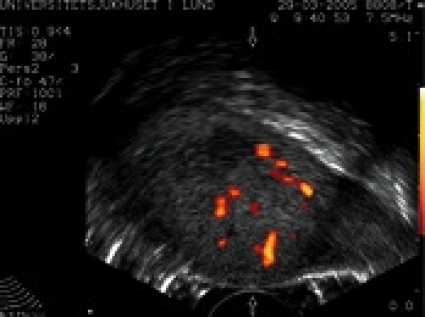

Vi upplever det värdefullt att utföra akut skrotalundersökning med rektalprob på urologmottagningen av patienter med skrotala smärtor, där ingen stark misstanke om testistorsion föreligger. Identifiering av cirkulation i testikeln och eventuell hyperemi i epididymis sekundärt till epididymit kan ge stöd för att avstå från exploration. Oftast föreligger en normal kontralateral testikel som intern kontroll för den ovane (icke-radiologen/ urologen) som ett stöd i ultraljudsdiagnostiken. Med ökad medvetenhet om metodens tillgänglighet och med riktad utbildning av urologer tror vi att metoden kan användas för att minska andelen akuta skrotala explorationer där torsion inte föreligger.